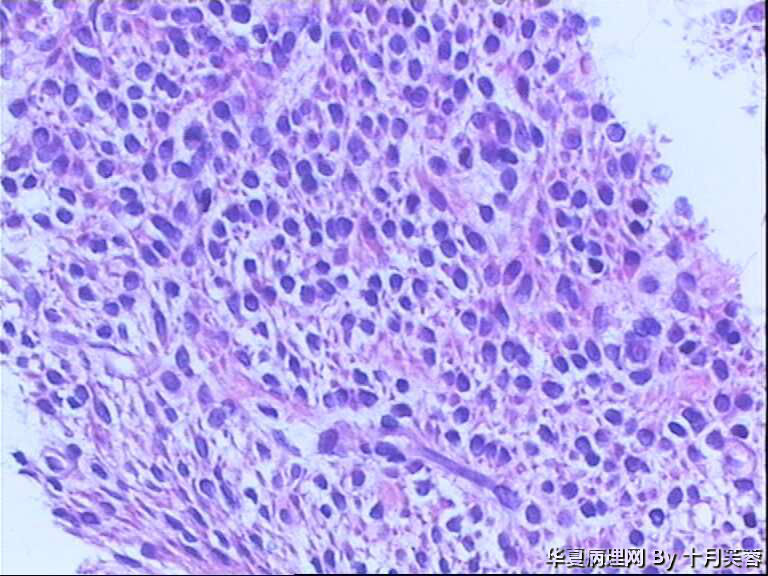

女性,50岁,临床申请单“子宫肌瘤穿刺”

• 子宫肌瘤穿刺图2

图2

平滑肌瘤?间质肿瘤?

具体到这一例,感觉要是子宫肌瘤的话则问题不大。但若是GIST,PECOMA,SFT等则不好说了!